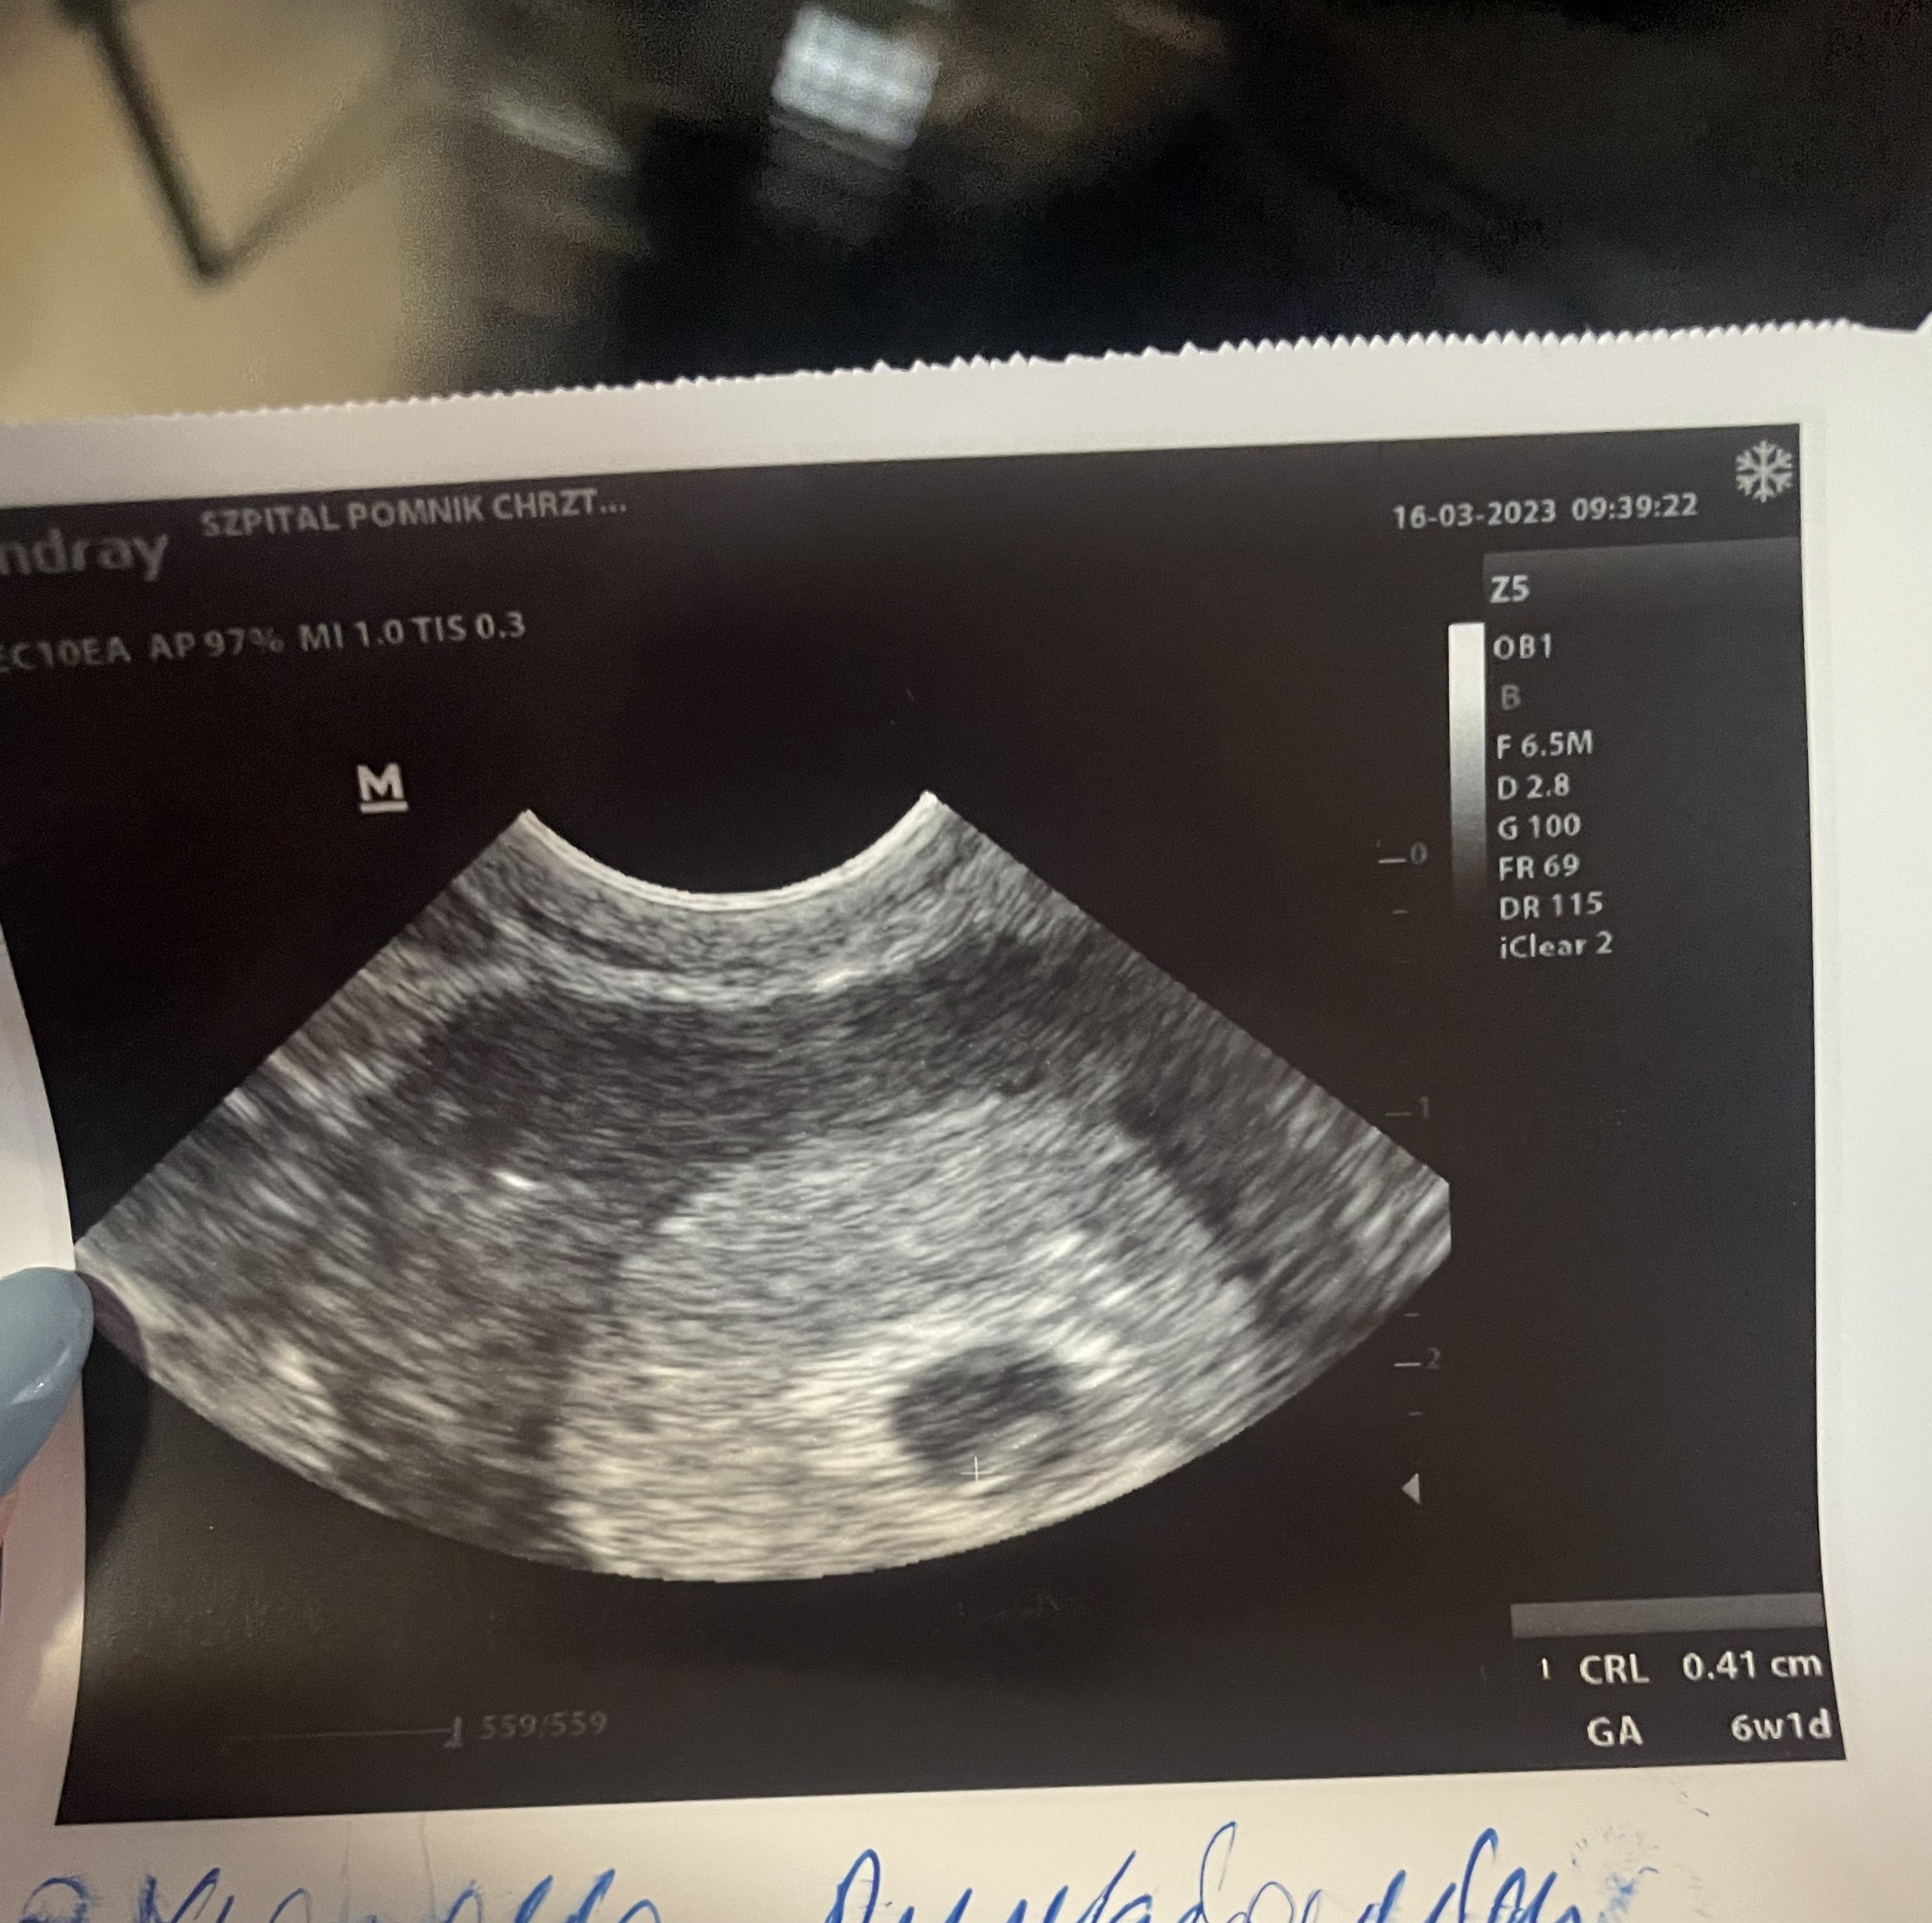

Dziewczyny jest serduszko, jest i bije 😭❤️😭❤️

6+1 wiec proszę o przepisanie mnie na 8 listopada. Nie watpcie w swoje kropeczki tak jak ja, nie wolno ! Ja już nie zwątpię nigdy i Wam tez zabraniam 😭✊